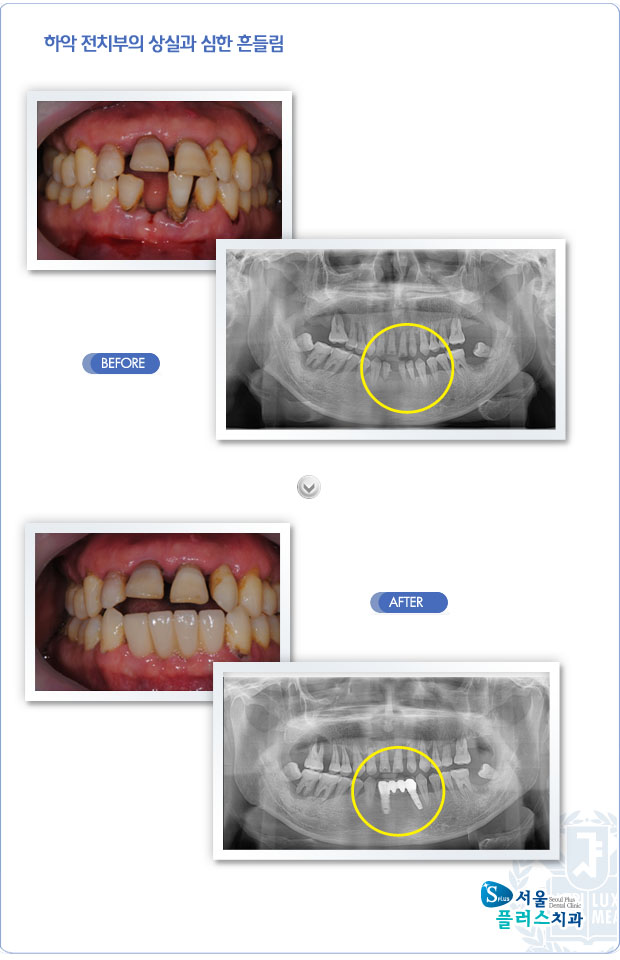

[임플란트] 하악 전치부의 상실과 심한 흔들림